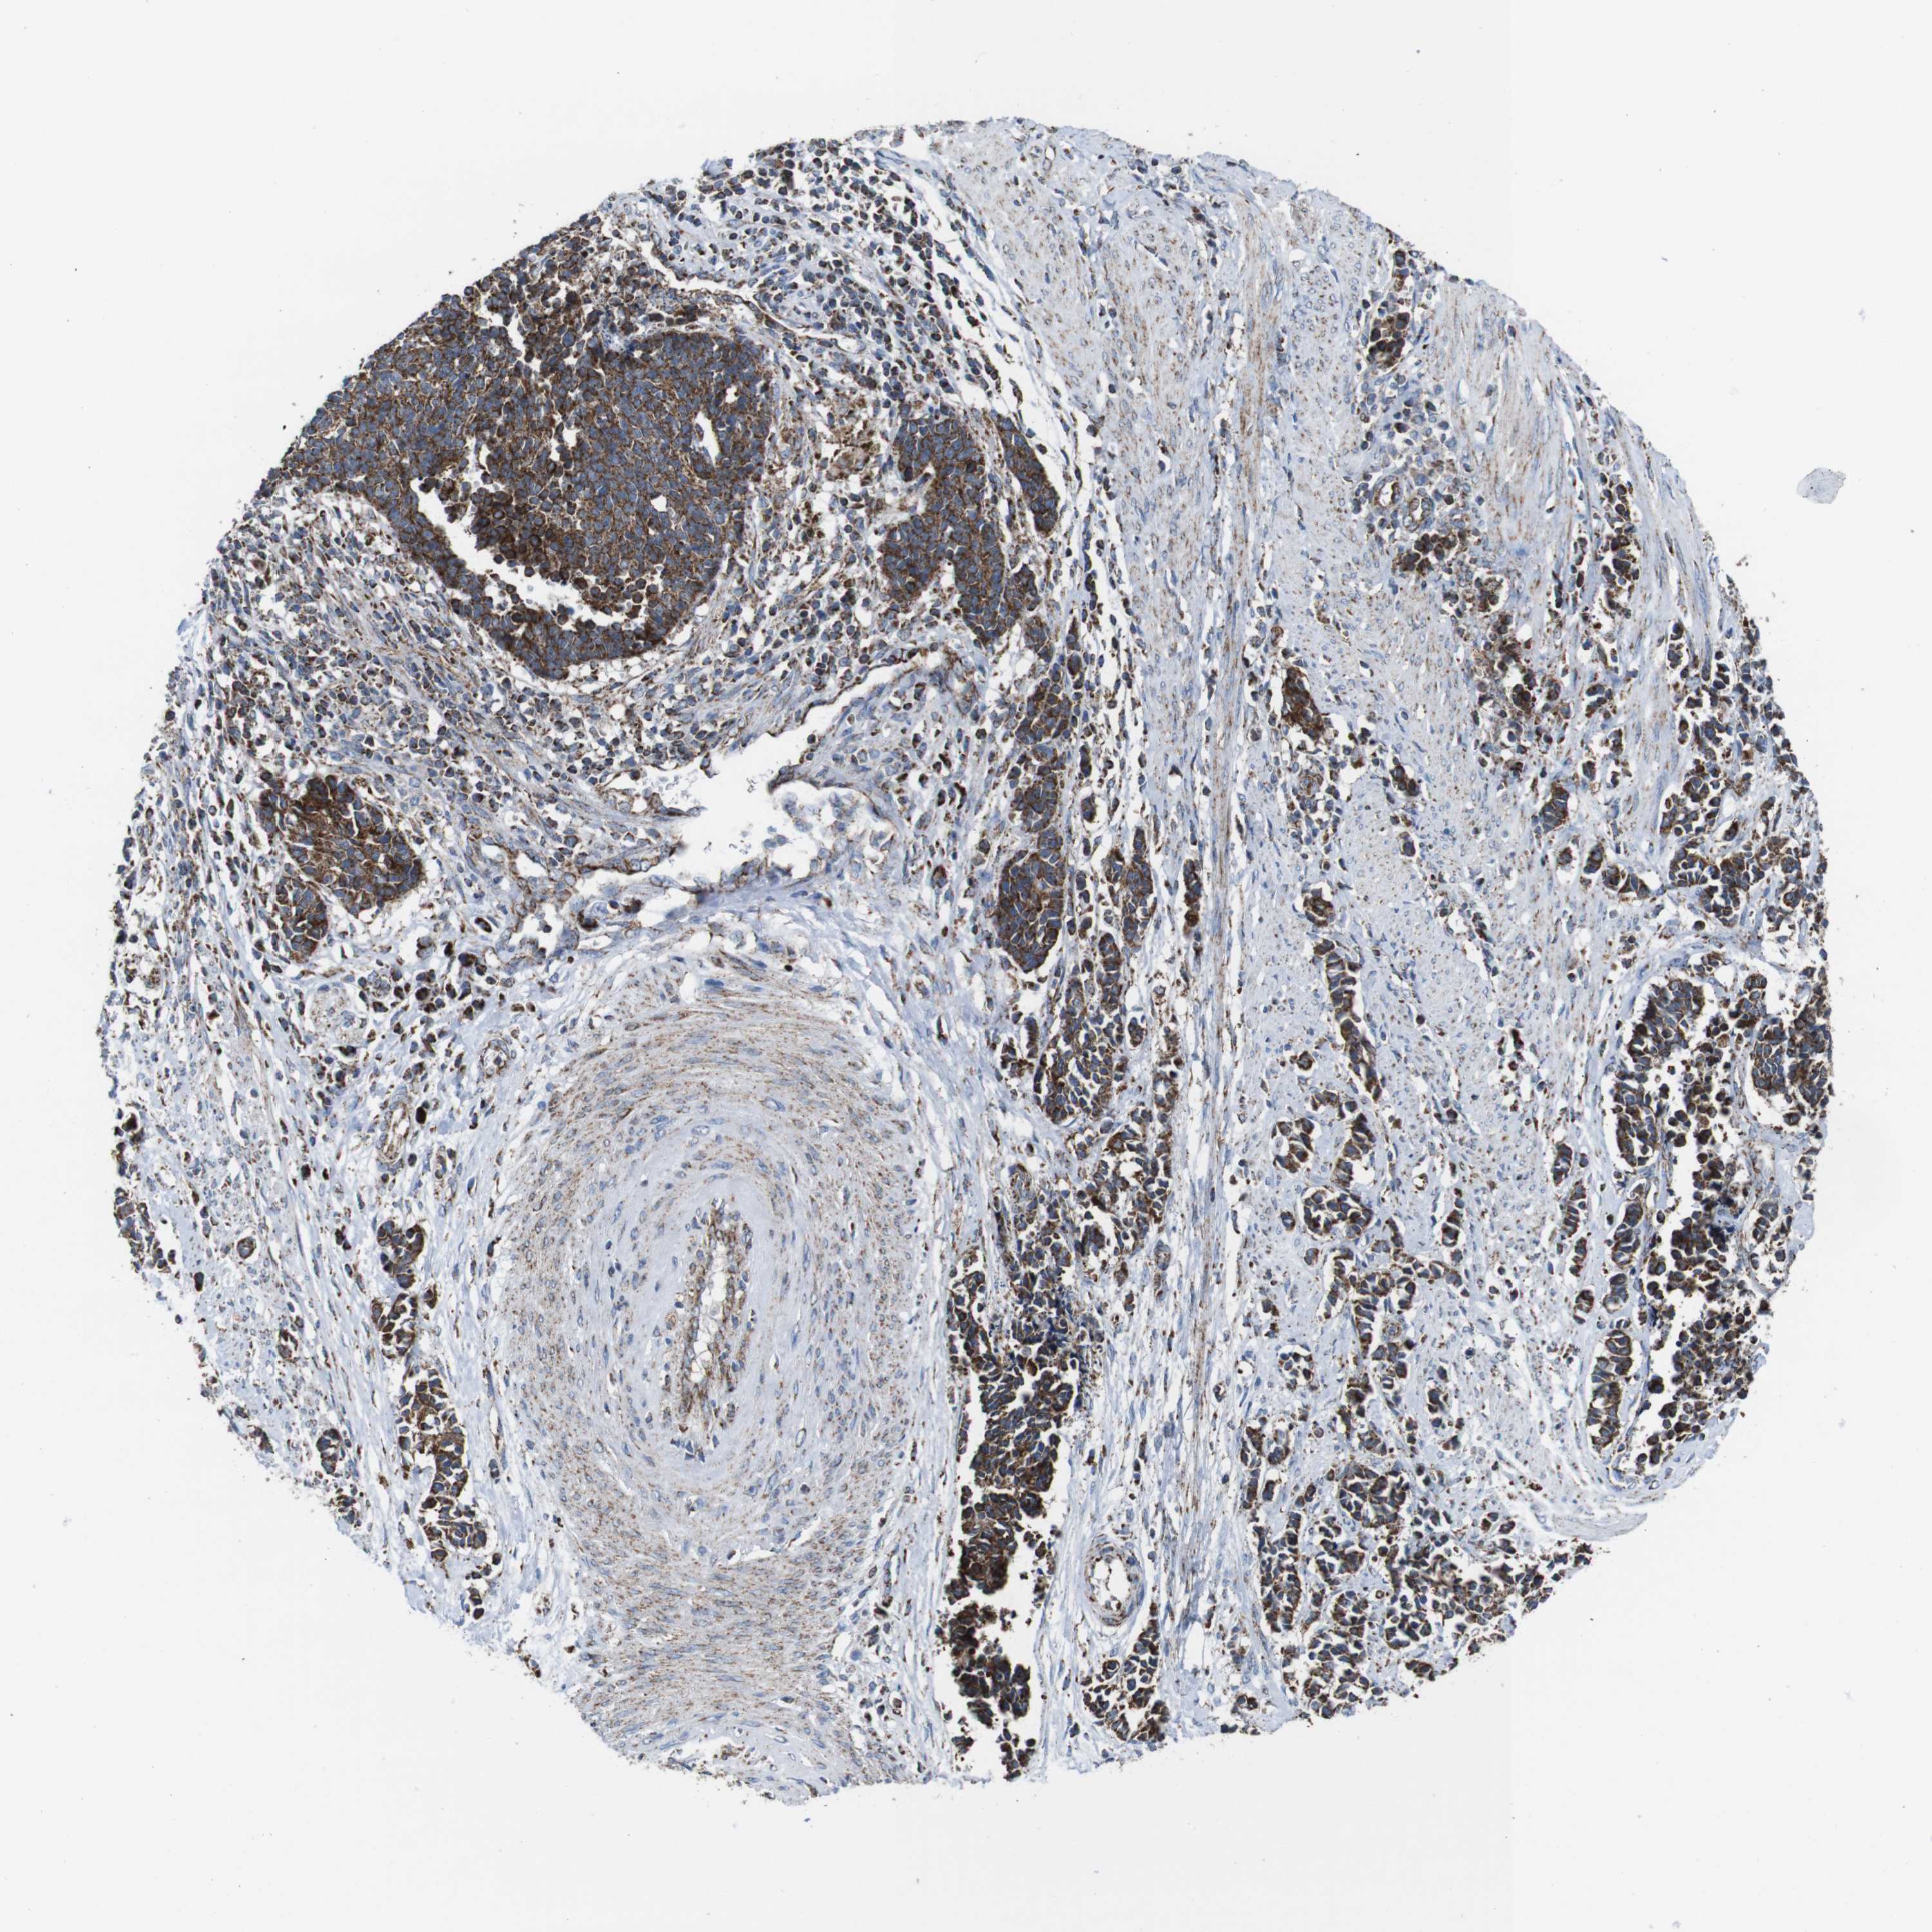

CERVICAL CANCER - Protein expressioni

A mouse-over function shows sample information and annotation data. Click on an image to view it in a full screen mode. Samples can be filtered based on level of antibody staining by selecting one or several of the following categories: high, medium, low and not detected. The assay and annotation is described here.

Note that samples used for immunohistochemistry by the Human Protein Atlas do not correspond to samples in the TCGA dataset.

Antibody stainingi

Antibody staining in the annotated cell types in the current human tissue is reported as not detected, low, medium, or high, based on conventional immunohistochemistry profiling in selected tissues. This score is based on the combination of the staining intensity and fraction of stained cells.

Each image is clickable and will lead to virtual microscopy that enables deeper exploration of all samples and also displays staining intensity scores, fraction scores and subcellular localization as well as patient and tissue information for each sample.

Antibody HPA007043

Antibody HPA007044

Antibody CAB010052

Squamous cell carcinoma, NOS

Adenocarcinoma, NOS